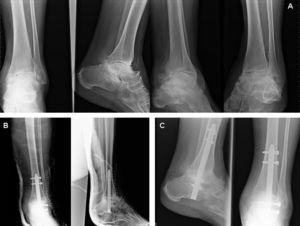

Tras el estudio preoperatorio habitual, se realizó la intervención quirúrgica (fig. 2) bajo anestesia general (3 casos) o raquianestesia (5 casos), y se aportó en uno de los 8 pacientes (paciente con seudoartrosis de un intento previo de artrodesis con fijador externo tras fractura de tobillo) injerto autógeno de cresta ilíaca por la importante pérdida ósea.

Caso n.o 2. A) Imágenes clínicas del paciente que muestran el varo del retropié y las cicatrices previas. B) Imágenes radiográficas iniciales que muestran la seudoartrosis tras el intento previo de artrodesis. C) Imágenes radiográficas iniciales que muestran la seudoartrosis al final del período de seguimiento.